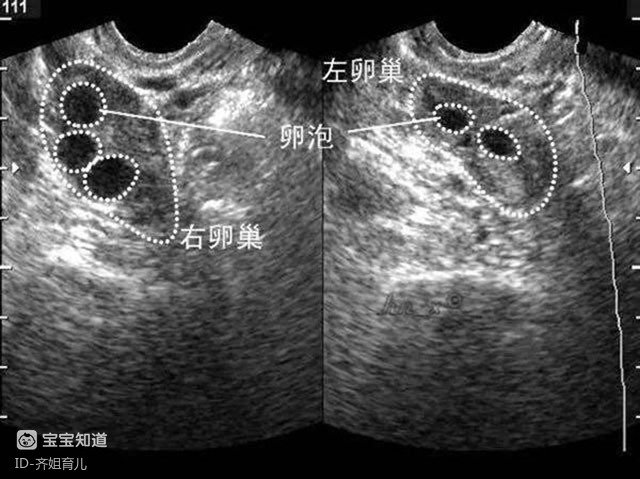

促排卵的過(guò)程根據(jù)每個(gè)人體質(zhì)的不同可能要持續(xù)一到兩周,主要是注射兩種促性腺激素來(lái)加速卵泡的成熟。

在這個(gè)過(guò)程中,要通過(guò)B超監(jiān)測(cè)卵泡的成熟情況,當(dāng)卵泡發(fā)育到18毫米以上就可以了。